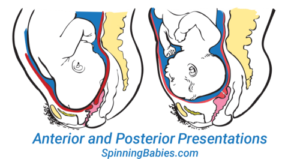

Your baby’s position inside the uterus is called their fetal position or fetal presentation. The ideal position is a Cephalic Presentation which means that the baby’s head is down. The most common form of Cephalic Presentation is the Vertex Presentation which is referring to the crown of the baby’s head leading into the birth canal path.

Meaning Anterior (A) referring to your back, near the pubic bone, Posterior (P) referring to your front, near the abdomen or Transverse (T) referring to halfway between Anterior and Posterior.

Most Optimal Position for Vaginal Birth

The Left Occiput Anterior (LOA) is known as the most optimal position for birth because it is one of the positions to help baby be in the smallest diameter to fit the pelvis. The crown of the LOA baby’s head most often enters the pelvis first, tucking the chin which helps the baby fit in a way that the baby’s head can mold/shape most effectively. The baby’s back can curve most effectively in this position as well. The baby slides down the softening abdomen to enter the brim. (https://www.spinningbabies.com)